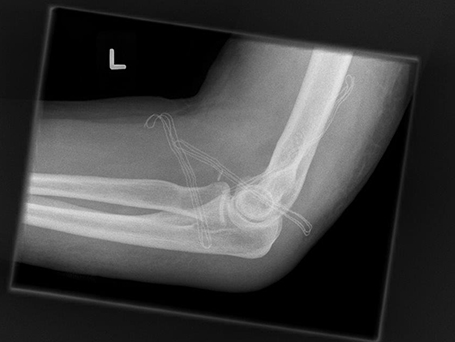

Die Operation dieser komplizierten Verletzungen zielt darauf ab die verletzten Bandansätze (ulnares und radiales Seitenband, beugeseitige Kapsel) wie auch die knöchernen Verletzungen (Speichenköpfchenbruch – oft zertrümmert, proc. Corornoideus) stabil wieder her zu stellen. Ziel ist es das Ellenbogengelenk frühzeitig stabil zu bewegen, um eine Einsteifung zu verhindern.

Rechtshändiger Fotograf mit hoch instabiler Ellenbogenluxationsverletzung links. Operative Stabilisation mit Rekonstruktion der Bandstrukturen des Ellenbogengelenkes außen und innenseitig unter Einsatz einer Augmentationstechnik (Internal Bracing).

Reponiertes Gelenk nach operativer Stabilisation

Ellenbogengelenk zentriert nach Operation frontal

Ellenbogengelenk zentriert nach Operation seitlich